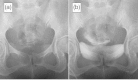

A woman with ascites and oliguria

Keywords: bladder rupture; pseudo-renal failure; urinary ascites.